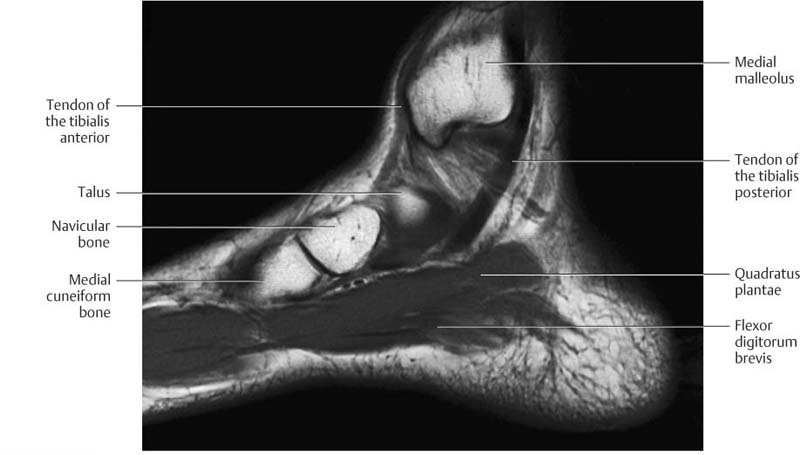

MRI Of The Foot | Radiology Key

radiologykey.com

radiologykey.com

mri foot radiology

Ankle And Foot | Radiology Key

radiologykey.com

radiologykey.com

foot ankle radiology fig radiologykey

Ankle And Foot | Radiology Key

radiologykey.com

radiologykey.com

foot ankle axial radiology medial sole lateral radiologykey

Ankle And Foot | Radiology Key

radiologykey.com

radiologykey.com

foot ankle radiology fig